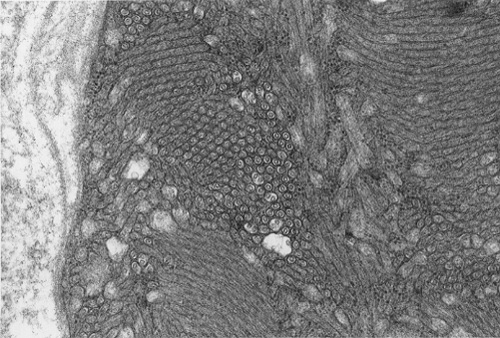

Pathology of the case: On hematoxylin-eosin stained frozen sections, there are many stongly basophilic, irregular subsarcolemmal depositions (Panel A and B). There is no significant variation in fiber diameter, increase in centrally located nucleus, inflammation, necrotic fiber, regenerating fibers or target fibers. These deposits appear bright red on modified Gomori's trichrome (Panel C). On ATPase reaction at pH 4.6 (dark fibers are type 1, pale fibers are type 2a while intermediate-intensity fibers are type 2b), there is no fiber type predominance (Panel D). Although the deposits are not visualized in the ATPase preparation, they are strongly reactive in NADH-TR reaction. Intesestingly, these deposits are not visualized in another preparation of oxidative enzyme- succinate dehydrogenase (Panel F). On the adenylate deaminase preparation, these deposits are strongly reactive (Panel G). The subsarcolemmal deposits are well visualized under the electron microscope which is electron dense (Panel H). On cross sections, these deposits are bundles of densely packed polygonal to round tubules with double walls that are arranged in small fascicles (Panel  I and J). The tubules are about 50-80 nm in diameter. The tubular aggregates also arrange in longitudinal bundles that run along the myofibrils (Panel K).

On resin embedded semithin sections, tubular aggregates may measure over 40 mm in length on longitudinal sections. At the ultrastructural level, tubular aggregates appear as masses of bundles of long, straight, parallel tubules in between myofibrils especially beneath subsarcolemmal locations. They are often double barrel and contains an inner tube but they may be up to eight inner tubes. The outer tube is usually about 50 nm in diameter but may be as large as 80 nm. The inner tubules are 20-30 nm in diameter.